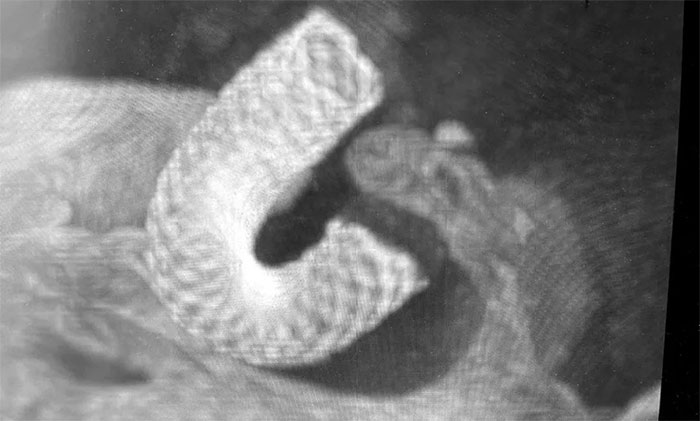

患者頭痛症狀明顯加重,結合動脈瘤形態及相關檢查,瘤體破裂風險較高,建議積極治療。該動脈瘤較理想的治療方式為血流導向裝置置入,它具有手術微創,相較於其他手術方式,減少對瘤體本身的擾動,安全性相對更高,在降低和防止動脈瘤遠期復發等方面也具有一定的優勢。經討論,大家一致認同該治療方案,與家屬詳細解釋溝通後,同意進行手術治療。

經充分完善術前準備,席剛明教授在麻醉科和介入手術室緊密配合下,開展右頸內動脈眼動脈段動脈瘤血流導向裝置(Pipeline)置入術。手術歷時兩個小時,順利“拆除”了埋在患者腦子裏的“不定時炸彈”。

▲ 造影顯示血流導向裝置貼壁良好

術後,患者無新發神經功能缺損,餘志良主任進一步為患者開展活血化瘀、改善腦循環、營養神經等中西醫結合對症治療,頭痛症狀基本消失,於近期康復出院。